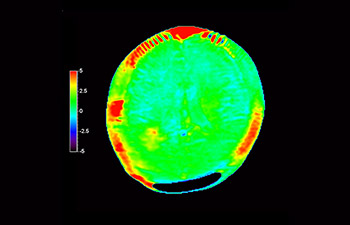

Neurologische Leiden stellen eine schwere Belastung dar. Philips hat es sich zum Ziel gesetzt, hochwertigste Neuro-Bildgebung zu ermöglichen – für eindeutige Diagnosen und eine schnelle Therapie. Wenngleich die MRT heutzutage den Goldstandard in der neuroradiologischen onkologischen Bildgebung darstellt, kann die Genauigkeit beim Tumor-Grading und den Nachsorgeuntersuchungen noch weiter verbessert werden. 3D APT (Amide Proton Transfer) ist eine einzigartige, kontrastmittelfreie Methode zur MR-Tomographie des Gehirns, die den Bedarf nach einer sichereren Diagnose in der Neuroonkologie erfüllt. 3D APT nutzt das Vorhandensein von endogenen zellulären Proteinen zur Erzeugung eines MR-Signals, das direkt mit der Zellproliferation, einem Marker für Tumoraktivität, korreliert. 3D APT kann geschulte medizinische Fachkräfte dabei unterstützen, gering differenzierte von hochdifferenzierten Gliomen und Tumorverhalten von Behandlungseffekt zu unterscheiden1.

APT wurde bei etwa 70 MR-Untersuchungen von Kindern mit Hirntumor eingesetzt, und wir haben einige ermutigende Erstergebnisse.“

John Curran, MD

Radiologe am Phoenix Children’s Hospital (PCH)